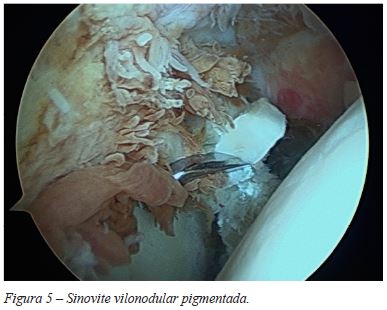

A doente foi submetida a artroscopia do ombro tendo sido constatada extensa sinovite (Figura 5), com suspeita de sinovite vilonodular pigmentada. Foi realizada sinovectomia total (Figura 6), com envio de amostras de tecido para estudo histológico. Foram realizadas também acromioplastia e sutura do SSP com dois sistemas de âncoras.